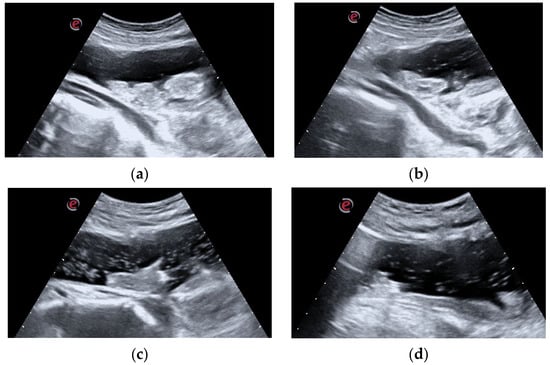

Under direct vision, the clot was progressively fragmented with the aid of the cystoscope, compressing the clot against the neobladder wall and weakening it. The vacuum effect of the 60 mL syringe permitted a progressive clot reduction into smaller fragments, which were progressively evacuated (Figure 3).

Intraoperative image: the evacuative approach is clearly shown. The 14 Ch urethral sheath is inserted into the Mitrofanoff. All operative channels are closed in this phase, while a 60 mL syringe is whipped at the optical access. The surgeon’s left hand firmly holds the sheath, while the right one (not visible in this picture) is dedicated to clot aspiration.

Due to the limited degrees of movement, in order to not damage the appendicovesicostomy, the contemporary US examination was performed till complete clot disruption was achieved (Figure 4a–d).

(a–d). Intraoperative US evaluation: the intraoperative US examination improved the assessment of the progressive clot disruption till its complete disappearance. In image (a), the main clot components are clearly visible. During the successive phases, images (b,c), clot dimensions progressively decrease, while a corpuscular suspension occupies the filling liquid. Finally, image (d), the clot is no more visible and only small fragments float in the lumen.